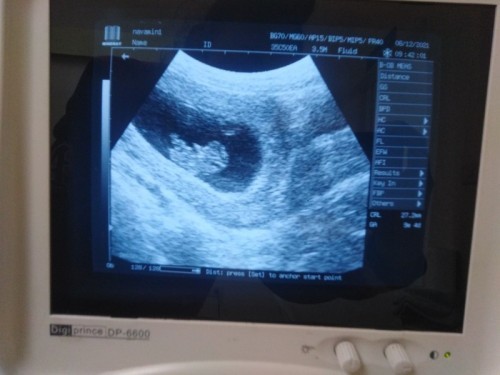

อัลต้าซาวด์ไม่ตรงกับในสมุดสีชมพู

ในสมุดหมอเขียน 10วีค พอซาวด์ได้ 9วีค 4วัน เเบบนี้ดูตามอายุครรภ์ตามอัลต้าซาวด์เลยใช่มั้ยคะ เเล้วคุณเเม่ที่อัลต้าซาวด์ครั้งเเรกปวดท้องมั้ยคะ หมอกดท้องคลำหาลูก ปวดค่ะเเต่ไม่มีเลือดออกนะคะ ปกติมั้ยคะกังวลมากกลัวจะมีผลกระทบต่อลูกค่ะ 🤦♀️#ขอบคุณสำหรับคำตอบค่ะ